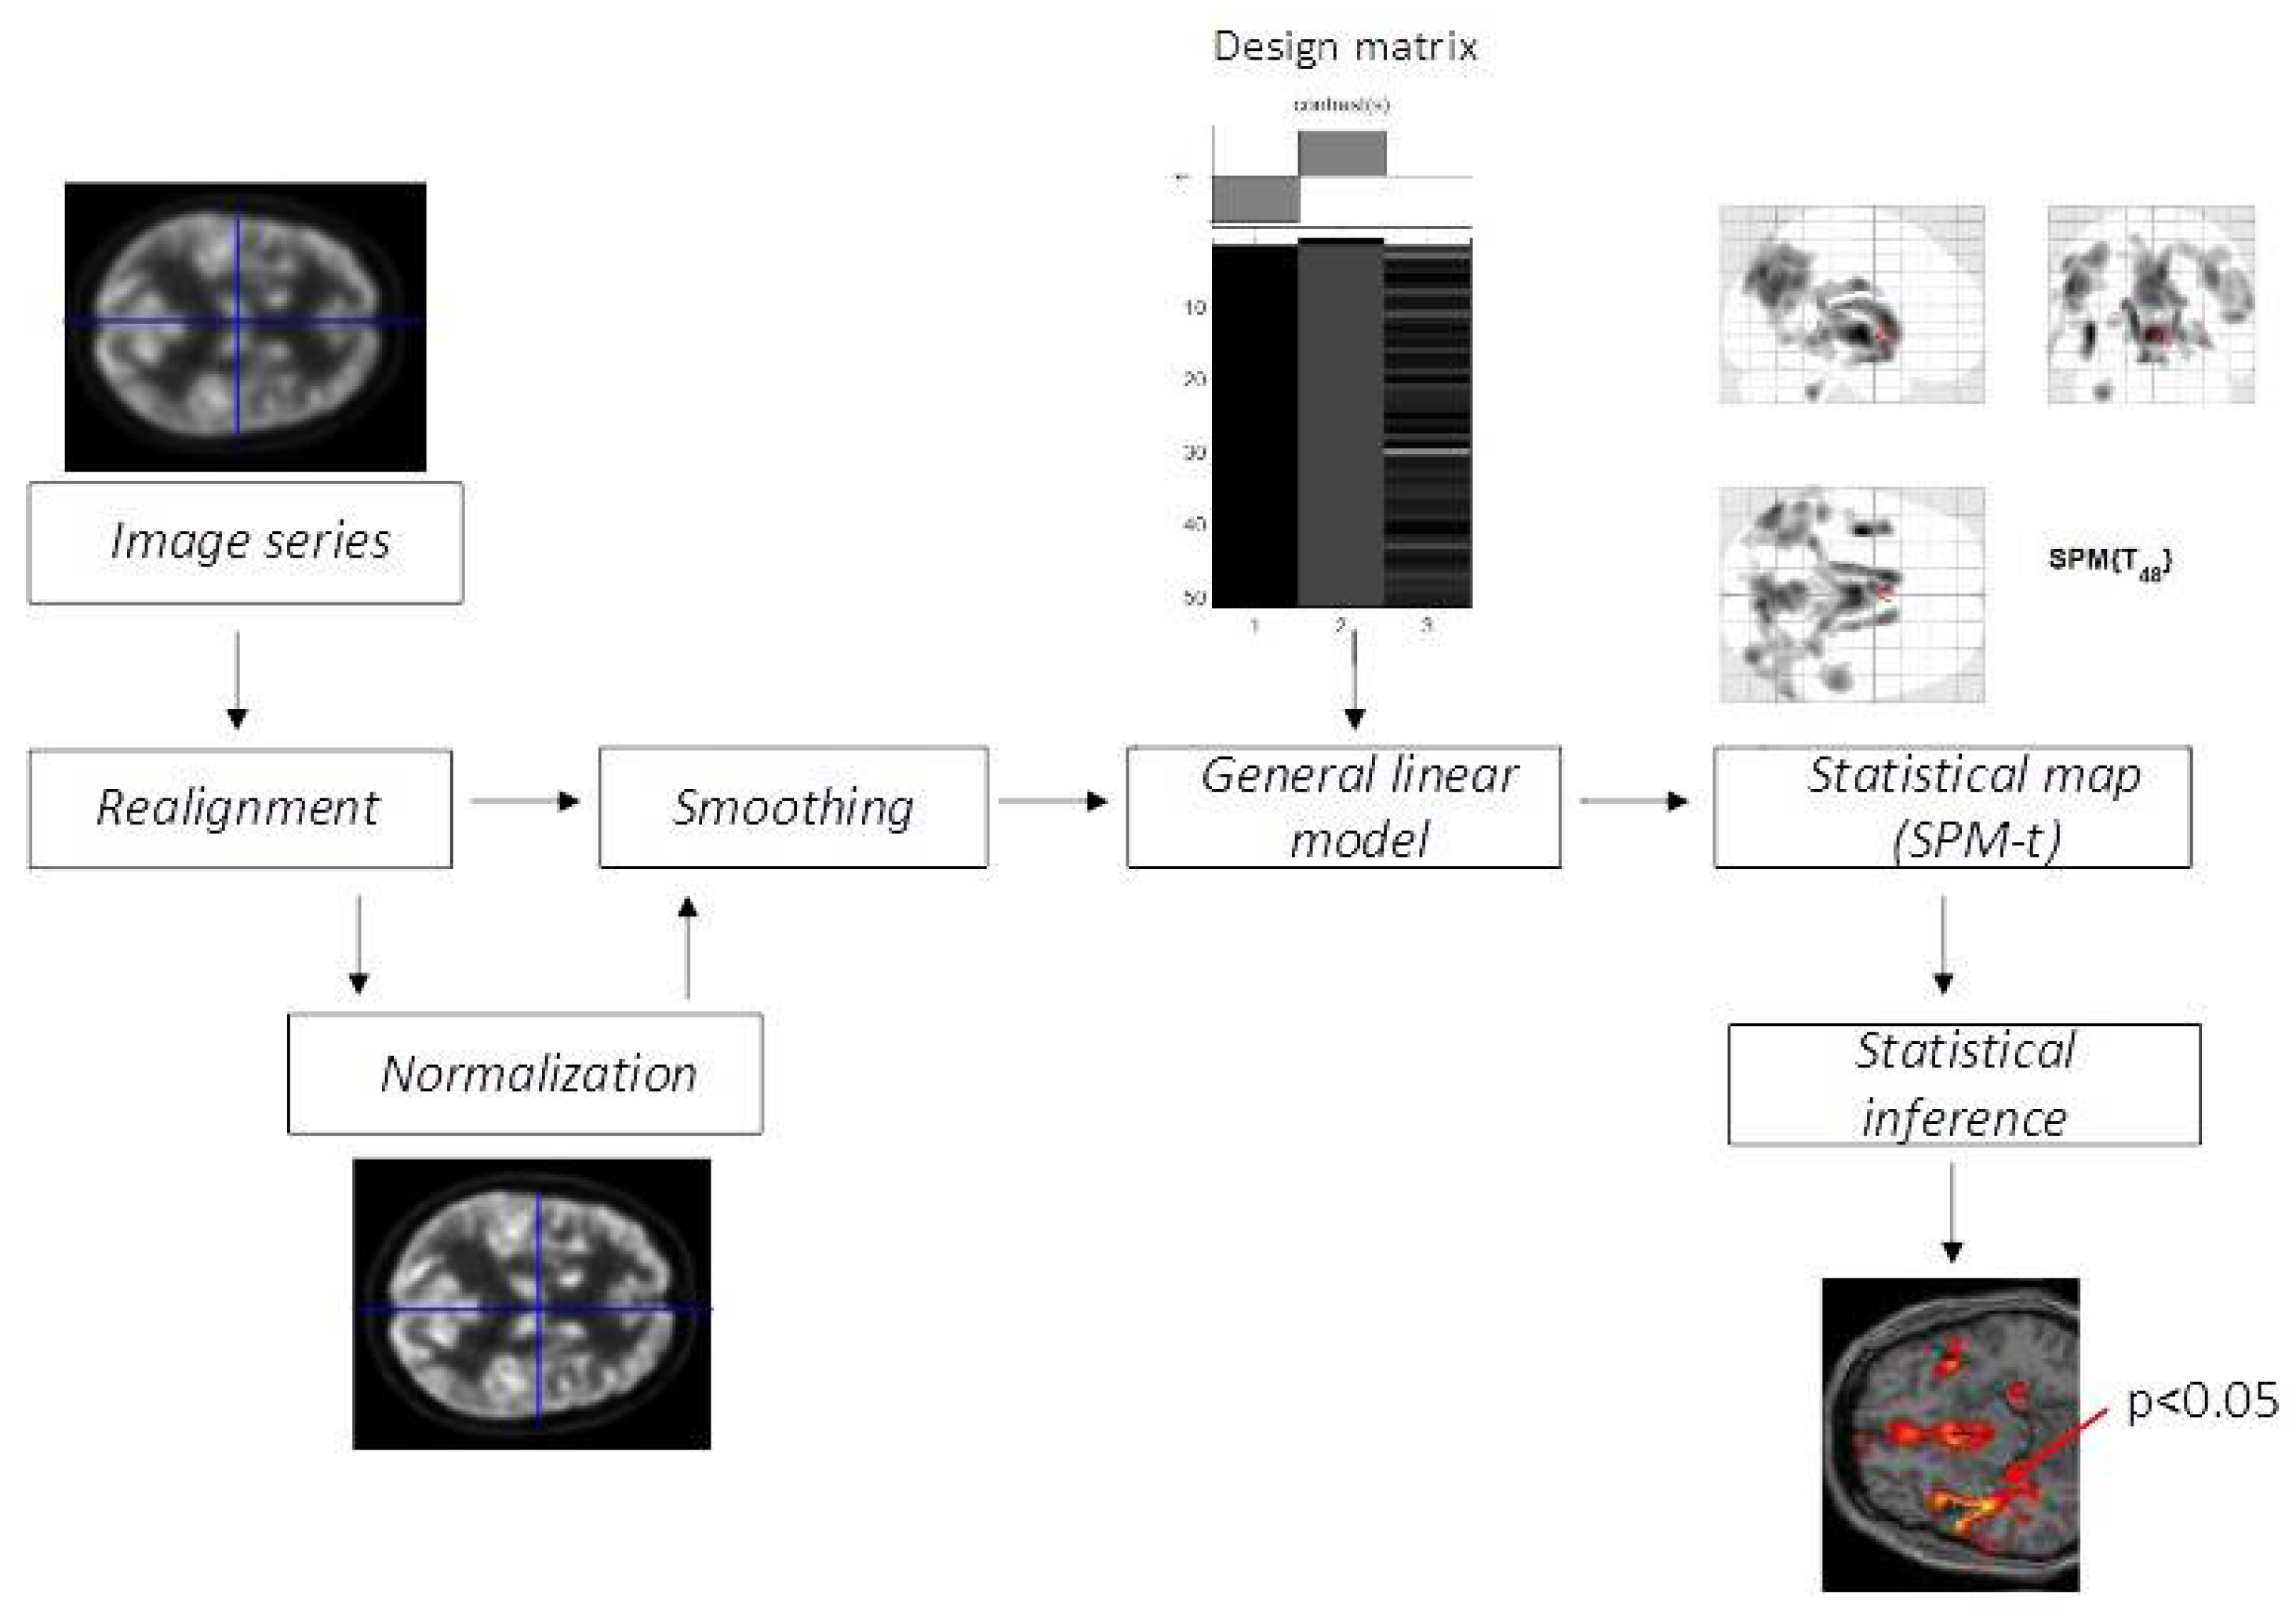

- Penny, W.D.; Friston, K.J.; Ashburner, J.T. (Eds.) Statistical Parametric Mapping: The Analysis of Functional Brain Images; Elsevier: London, UK, 2011. [Google Scholar]